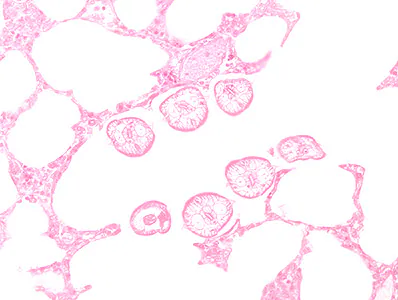

Several people developed gastrointestinal symptoms of watery diarrhea, nausea with vomiting, and low-grade fever approximately 1 week after attending a catered event. Stool specimens were collected for laboratory testing which included a formalin-ethyl acetate concentration with brightfield wet mount examination.